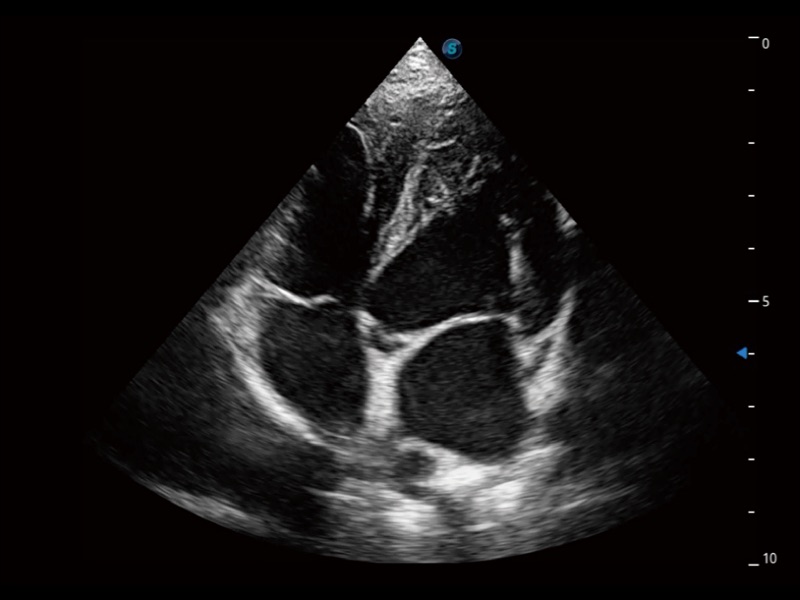

为精细结构及组织边缘提供高清晰度的图像和更大的成像视野。帮助减轻医生的用眼疲劳,快速精准获得测量的数据。